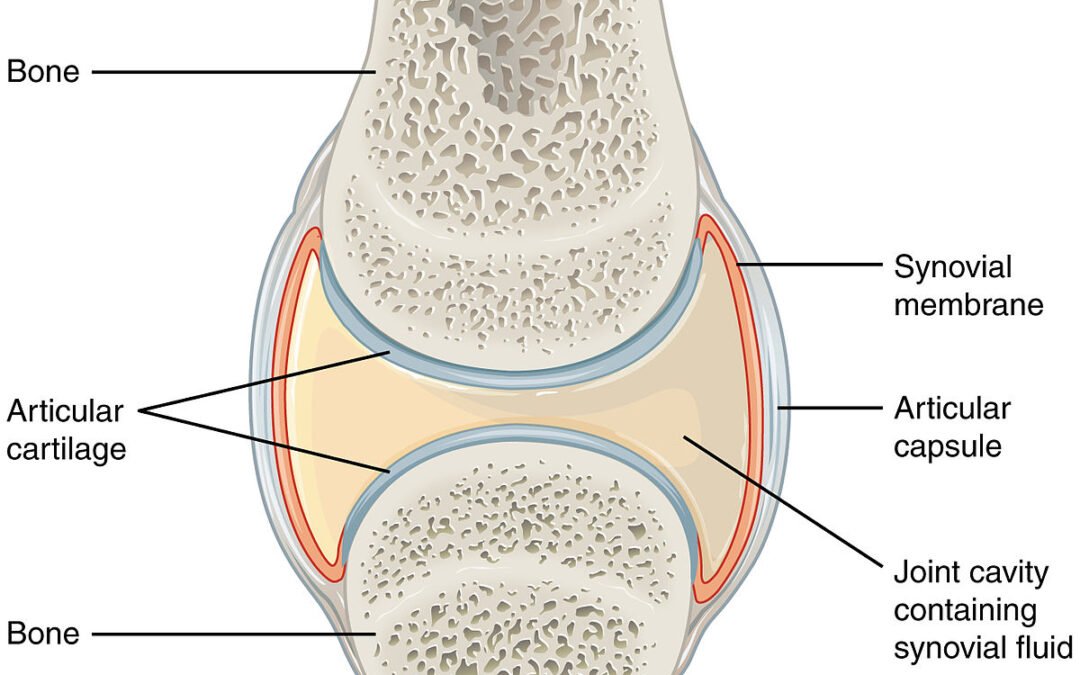

الكثير منا في هذه الايام يتعرض لآلام في نقاط معينة من الجسم وتعب وإرهاق مستمر وصعوبة في التركيز وألم في العضلات، كلنا نتساءل ما السبب؟ قد تكون مصاباً بالفايبروميالجيا التي تعتبر حالة مزمنة تتسم بالألم المزمن والتعب الشديد والحساسية المفرطة في الجسم. حيث يعاني الأشخاص...